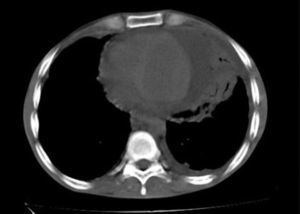

Paciente masculino, de 25 años, con antecedente de epilepsia tratada con carbamazepina, quien consultó por fiebre hasta 40°C, tos seca y dolor torácico retroesternal de una semana de evolución. Al examen físico: FC: 90 lat/min, FR: 30 vent/min, PA: 100/60mm Hg, °T: 37°C. Cuello sin adenopatías palpables, sin ingurgitación yugular; ruidos cardíacos rítmicos, sin frote pericárdico. Murmullo vesicular universal con crépitos bibasales; abdomen blando con hígado palpable a 3cm por debajo de reborde costal derecho; extremidades eutróficas, sin edemas y con fuerza muscular conservada. No había lesiones en piel. La radiografía del tórax evidenció silueta cardiomediastínica aumentada de tamaño, que no permitía valoración del parénquima pulmonar izquierdo. La tomografía del tórax reveló opacidades alveolares basales bilaterales por proceso inflamatorio y presencia de derrame pericárdico y derrame pleural izquierdo (fig. 2). Recibió tratamiento con ampicilina sulbactam y claritromicina. El ecocardiograma documentó derrame pericárdico grande y signos inminentes de taponamiento. Se realizó ventana pericárdica con biopsia pericárdica que mostró fibrosis con inflamación crónica no granulomatosa, negativa para malignidad. Los exámenes de laboratorio fueron positivos: ANAs 1/640 patrón moteado, Ac ANTI DNA 1/1772, linfopenia 720 células/microlitro. Con criterios inmunológicos y clínicos (poliserositis) para LES, se inició manejo con prednisolona, cloroquina y micofenolato de mofetilo, sin recurrencia del derrame pericárdico durante seguimiento ambulatorio a las ocho semanas.